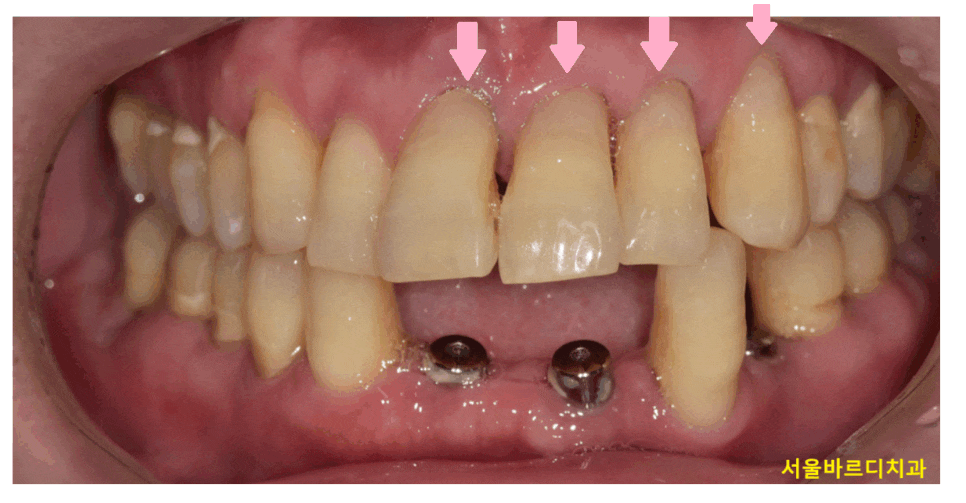

사진을 한번 봐볼까요~?

치아가 잇몸쪽 부위가 파여있죠~?

이런 증상을 우리는 치경부마모증이라고 부릅니다.

치아와 잇몸이 만나는 부분

치아의 목 부분이기 때문에 치경부라 말하는데요.

이 부위가 마모되어 치아가 깎여 나간 상태를 뜻합니다.

241224 치아 목 부위 = 치경부